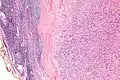

IPMs are diagnosed by examination of the tissue by a pathologist. They have a rim of peripheral lymphoid tissue (remnant of a lymph node) and consist of spindle cells with nuclear palisading. Red blood cell extravasation is common and blood vessels surrounded by collagen with (fine) peripheral spokes (amianthoid fibers) are usually seen.[2]

Immunostains for smooth muscle actin and cyclin D1 are characteristically positive. The main histologic differential diagnosis is schwannoma.

Low mag. -